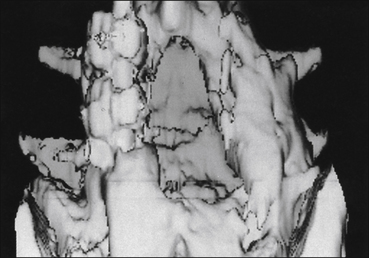

Figure 71-5 Three-dimensional reconstruction demonstrating the previous laminectomy and fusion.

These views are most useful in reconstructing the post-surgical changes and in assessing fusion stability; remember that the averaging techniques used will always overstate the solidity of the fusion.